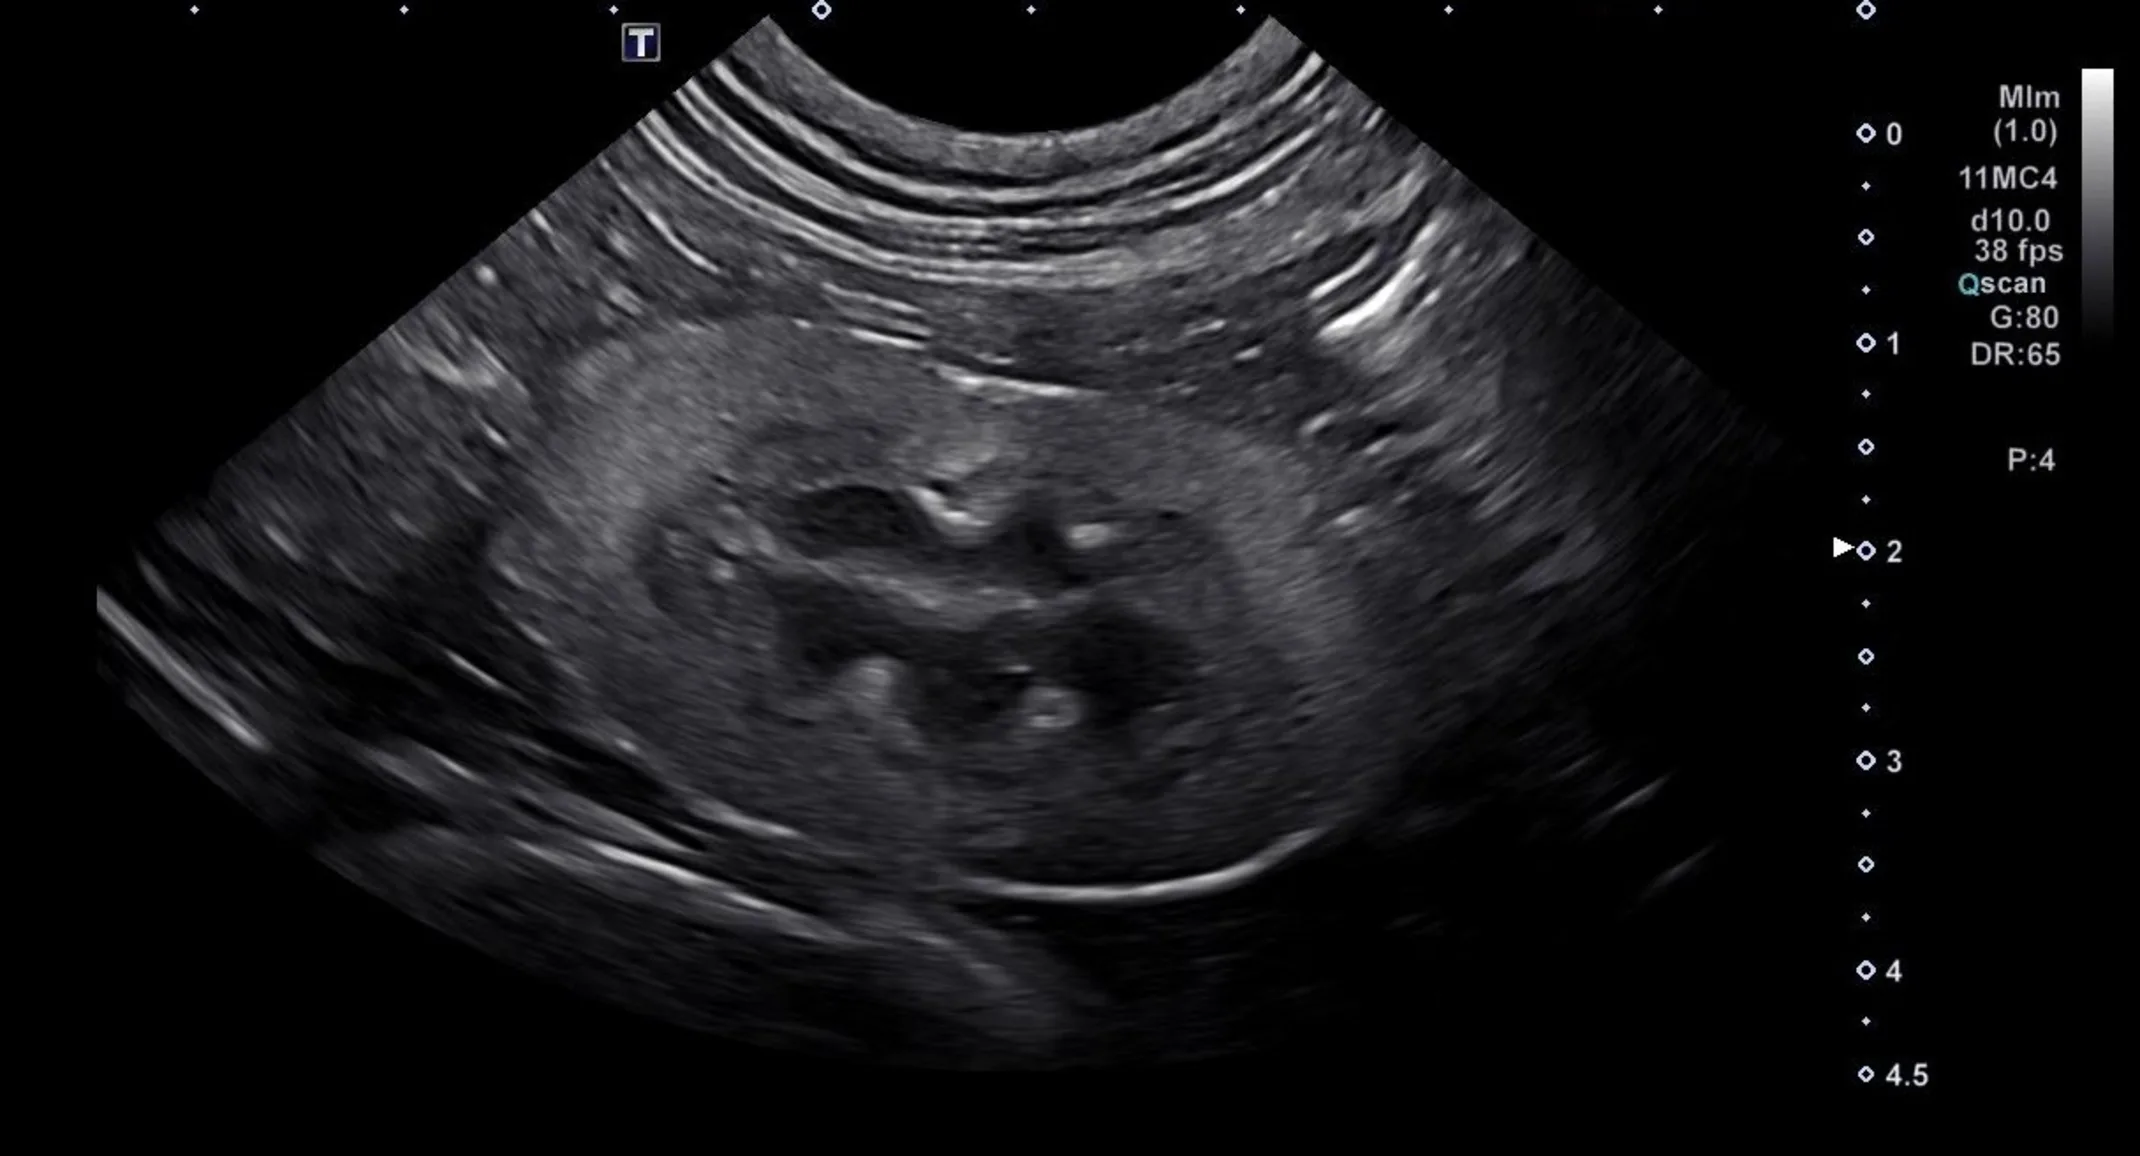

However, CKD can be complex. Some cats may develop additional complications, have atypical lab results, or require specialized imaging such as ultrasound to assess the kidneys’ structure. This is where a veterinary specialty team, such as the VERC Internal Medicine team, can provide advanced care and guidance.

- Requires advanced diagnostics. Ultrasounds, imaging, and specialized lab tests can provide insights that standard bloodwork might miss. This helps identify the exact cause of kidney changes and rule out other conditions.

- Advanced diagnostics. Bloodwork, urinalysis, ultrasounds, and sometimes more specialized testing help pinpoint the severity of kidney disease and rule out other conditions.